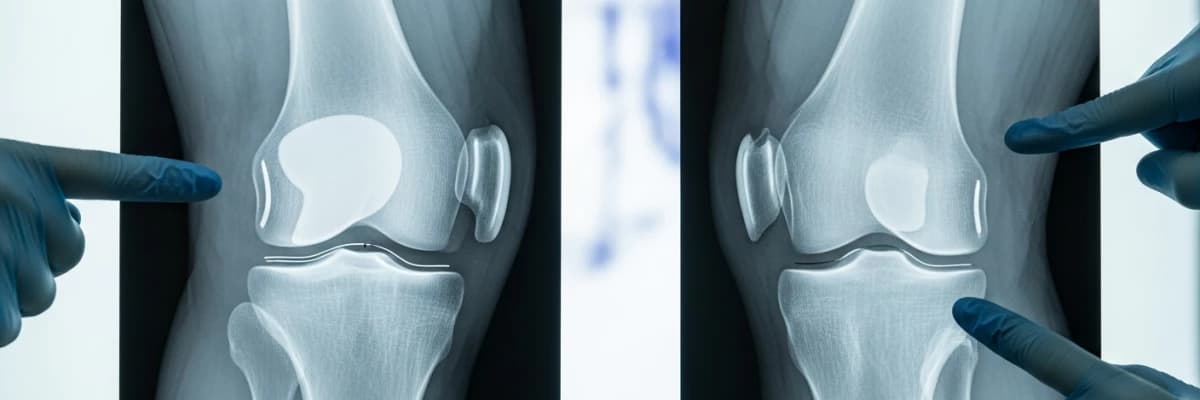

Unikondiler diz artroplastisinde (UDA) aseptik gevşeme başarısızlığın en önemli nedenlerinden biridir. Bu çalışmanın amacı, tasarımcı olmayan bir grup kohortunda çimentosuz ve çimentolu UDA’lar arasındaki erken fizyolojik ve patolojik radyolusent hatları (RLH) karşılaştırmaktı.

Bu çalışmada 2012-2018 yılları arasında 38 çimentolu UDA ve 47 çimentosuz UDA uygulanan iki hasta grubu retrospektif olarak karşılaştırıldı. Hastaların klinik sonuçlarının değerlendirilmesinde Oxford Diz Skoru, EQ-5D-3L, EQ-VAS ve KOOS skorlamaları kullanıldı. RLH’lerin varlığının değerlendirilmesinde, tibial ve femoral bileşen ara yüzleri bölgelere bölündü ve RLH’ler için değerlendirildi.

Klinik sonuçlar açısından gruplar arasında istatistiksel olarak anlamlı fark yoktu (p> 0, 05). Hiçbir hastada femoral veya tibial bileşen ara yüzlerinde tam RLH gözlenmedi. Tibial bileşen ara yüzünde parsiyel radyolusent bölgeler çimentolu UDA’larda 32 (% 11, 3) ve çimentosuz UDA’larda 13 (% 5, 7) bölgede tespit edildi. Tibial bileşen arayüzünde kısmi RLH görülme sıklığı ve toplam radyolusent bölge sayısı çimentolu artroplastilerde daha yüksekti (p= 0,040 ve p= 0,025).

Unikondiler diz artroplastisindegözlenen aşırı fizyolojik RLH’lerin hastaların klinik sonuçları üzerinde etkisi olmadığı tespit edildi. Fizyolojik RLH oranı çimentosuz UDA’da çimentolu UDA’ya göre önemli ölçüde daha düşüktü.